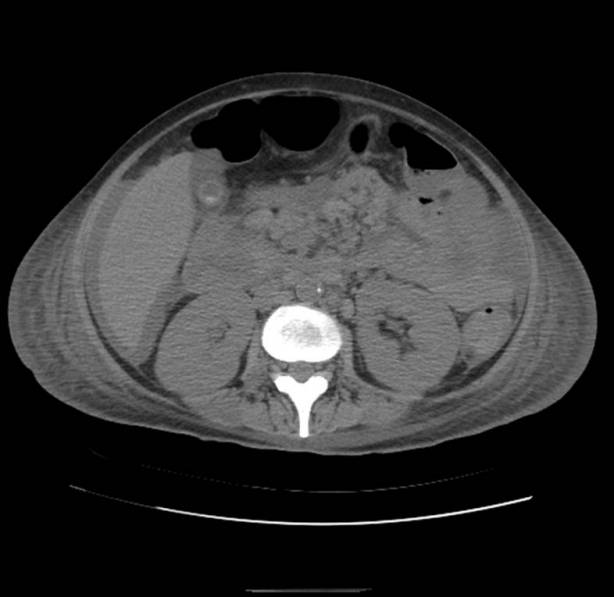

Figure 3.

Abdominal CT scan showing the improved ascites following MAC treatment. Notably, no change in the paraaortic and mesenteric lymph node enlargement was observed. CT, computed tomography; MAC, Mycobacterium avium complex.